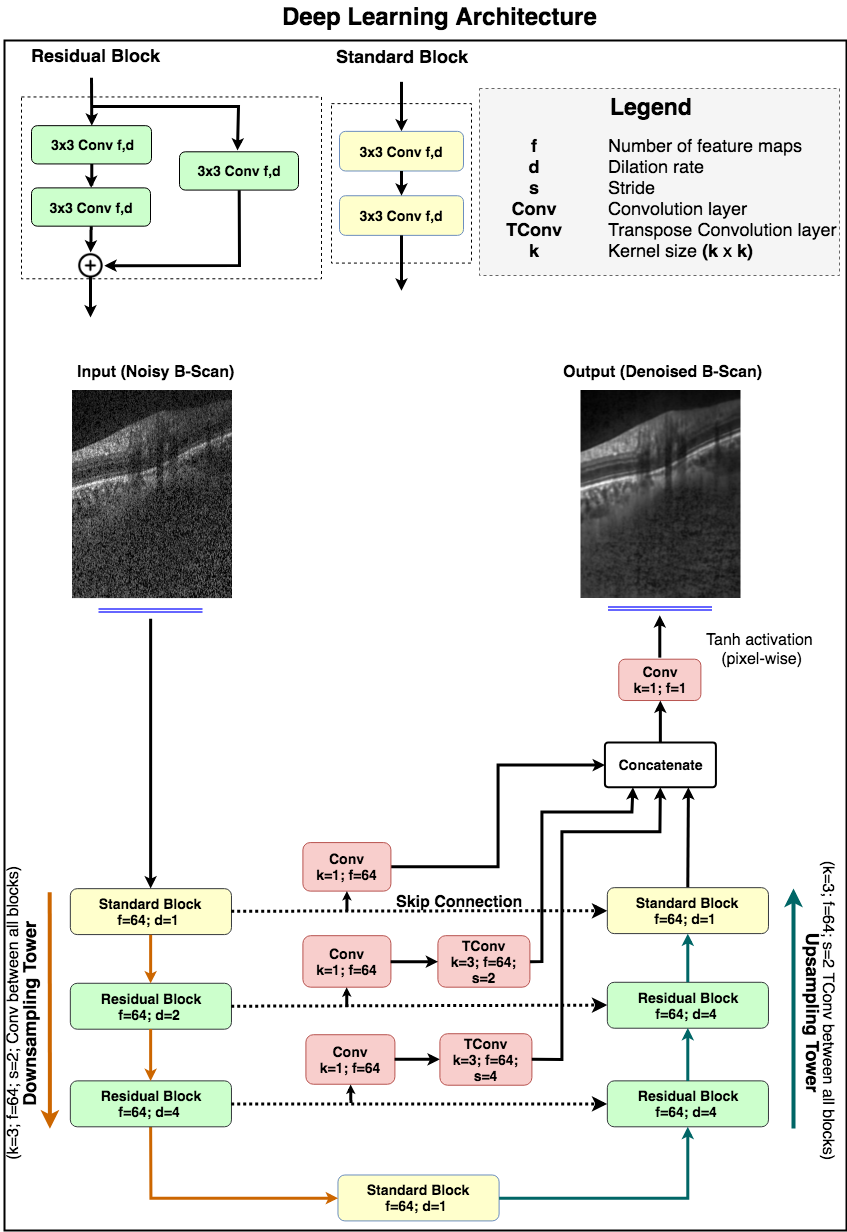

The network was composed of a downsampling and an upsampling tower, connected to each other via skip-connections (Figure 1). Each tower consisted of one standard block and two residual blocks. Both the standard and the residual blocks comprised of two dilated convolution layers (64 filters; size = 3x3). A 3x3 convolution layer was used to implement the identity connection in the residual block.

In the downsampling tower, an input B-scan (size: 496x384) was fed to a standard block (dilation rate: 1) followed by two residual blocks (dilation rate: 2 and 4, respectively). A convolution layer (64 filters; size = 3x3; stride = 2) after every block sequentially reduced the dimensionality, enabling the network to understand the contextual information.

The latent space was implemented as a standard block (dilation rate: 1) to transfer the feature maps from the downsampling to the upsampling tower.

The upsampling tower helped the network capture the local information. It consisted of two residual blocks (dilation rate: 4) and a standard block (dilation rate: 1). After every block, a transpose convolution layer (64 filters; size = 3x3; stride = 2) was used to restore the B-scan sequentially to its original dimension.

Multi-scale hierarchical feature extraction [71] helped recover tissue boundaries eroded by speckle noise in the single-frame B-scans. It was implemented by passing the feature maps at each downsampling level through a convolution layer (64 filters; size = 1x1), followed by a transpose convolution layer (64 filters; size = 3x3) to restore the original B-scan resolution. The restored maps were then concatenated with the output feature maps from the upsampling tower.

Finally, the concatenated feature maps were fed to the output convolution layer (1 filter; size = 1x1), followed by pixel-wise hyperbolic tangent () activation to produce a denoised OCT B-scan.

In both towers, all layers except the last output layer, were activated by an exponential linear unit (ELU) [72] function. In addition, in each residual block, the feature maps were batch normalized [73] and ELU activated before addition.

The proposed network comprised of 900,000 trainable parameters. The network was trained end-to-end using the Adam optimizer [74], and we used the mean absolute error as loss function. We trained and tested the proposed network on an NVIDIA GTX 1080 founders edition GPU with CUDA v8.0 and cuDNN v5.1 acceleration. With the given hardware configuration, each single-frame OCT B-scan was denoised under 20 ms.